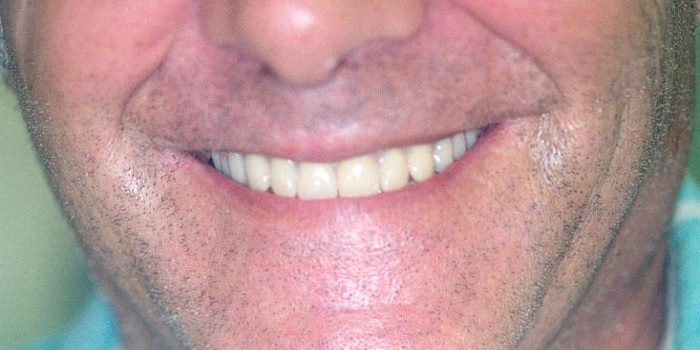

עם העלייה בגיל תופסים השתלים והתותבות את מקום השיניים הטבעיות. התותבות מהוות למעשה תחליף לשיניים שאבדו, ומקנות חיוך בריא ומראה פנים צעיר יותר, מה שמעלה גם את הביטחון העצמי והתחושה הכללית של האדם בחברה שבה ליופי ולאסתטיקה תפקיד חשוב.

ביצוע תותבת שלמה ע"י רופא מיומן יביא שיפור אסתטי משמעותי בצורת הפנים ויעניק ביטחון עצמי רב. במקרים רבים שבהם הייתה נפילה של הרקמות בשל חוסר שיניים, ביצוע תותבת שלמה עשוי לתת פיתרון פלסטי למבנה השפה והלחי, לטשטוש קמטים, לפנים נפולות ולקבלת חיוך צעיר בגיל מבוגר.לעתים החלפת תותבת ישנה, בנוסף לשפור התפקוד עשויה לשפר את מבנה הפנים ולתת בטחון ואסתטיקה מדהימים.